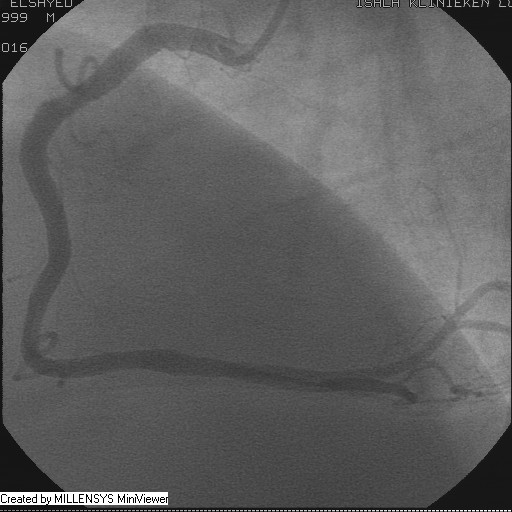

Patient transfered to Cardiac Catheterization Laboratory, coronary angiography showed atherosclerotic coronaries but without significant lesions, especially LAD that was patent with TIMI 3 flow (Figure 1- 5). Re-evaluation of the Angiography showed a small stump that can be for an occluded 1st diagonal (Figure 2a), at that level the LAD has a non-significant lesion.

Figure 3